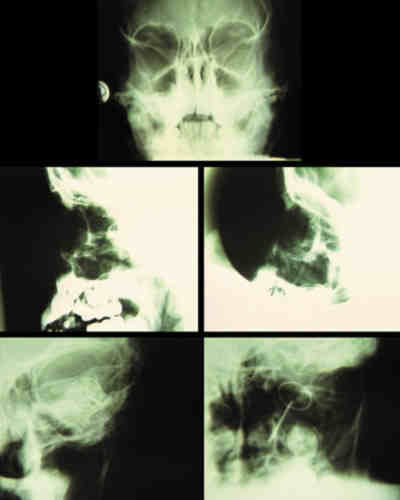

La utilización de Rayos X (figura 15) con proyecciones Caldwell, Waters, o las antero-posteriores pueden demostrarnos la presencia, pero no la localización, de un CEIO radiopaco y no detectará CEIO radiotransparentes, como la madera o el cristal. La ecografía nos ofrece una mejor localización del CEIO y es esencial para obtener información acerca de otros cambios estructurales como desprendimientos de retina o coroides. Al realizar esta exploración, han de tomarse precauciones para no comprimir el globo, sobretodo en los que presentan grandes heridas, y no producir prolapsos adicionales de su contenido. La ecografía con un estudio sistemático, con abordaje transversal y longitudinal puede determinar la localización del CEIO. La ultrasonografía biomicroscópica nos aporta algo más a la hora de diagnosticar cuerpos extraños ocultos o de polo anterior (123-125). La tomografía computerizada (TC) es el método diagnóstico de elección porque localiza y detecta CEIO radiopacos y radiotransparentes en 3 dimensiones. La TC tiene ciertas limitaciones y los CEIO metálicos crean artefactos significativos, que pueden dificultar la localización exacta. Esto puede ser un inconveniente a la hora de determinar si la localización de un CEIO es intrarretiniana o intraescleral. Asímismo la TC puede presentar problemas a la hora de identificar algunos CEIO de baja densidad, como la madera. Chacko, nos presenta en su artículo una interesante comparación entre la Tomografía Computerizada clásica (figura 16) y el TAC helicoidal (figura 17), demostrándose esta última más eficaz para la localización espacial de cuerpos extraños intraoculares o intraorbitarios (126).

63-15.jpg (11228 bytes)

Figura 15. Las distintas proyecciones de una radiografía de órbita, nos demuestran la presencia de cuerpos extraños radiosensibles, pero no la localización.